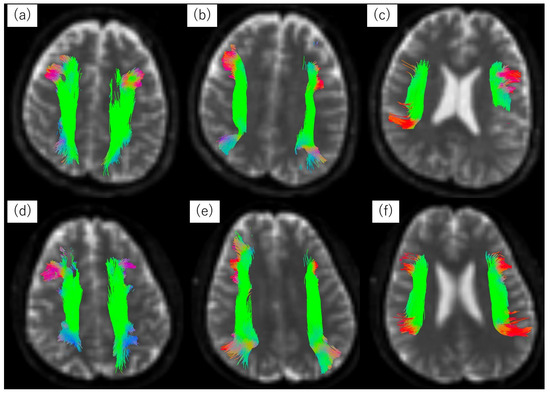

3.3. Tractography